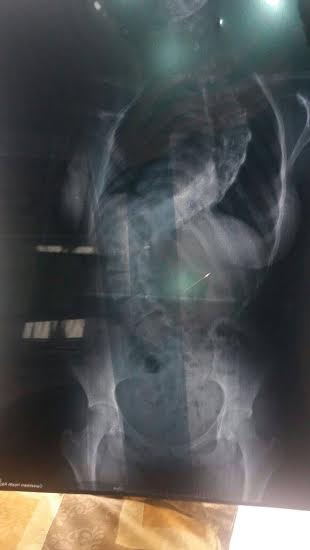

Olha só como esta a coluna de Manoela. Ela sente muitas dores.

É inconcebível que não haja encaminhamento para cirurgia imediata. É até uma questão de humanidade.

Laudo médico confirma que único tratamento é a cirurgia e se não for feita terá inclusive comprometimento de outros orgãos como o coração.